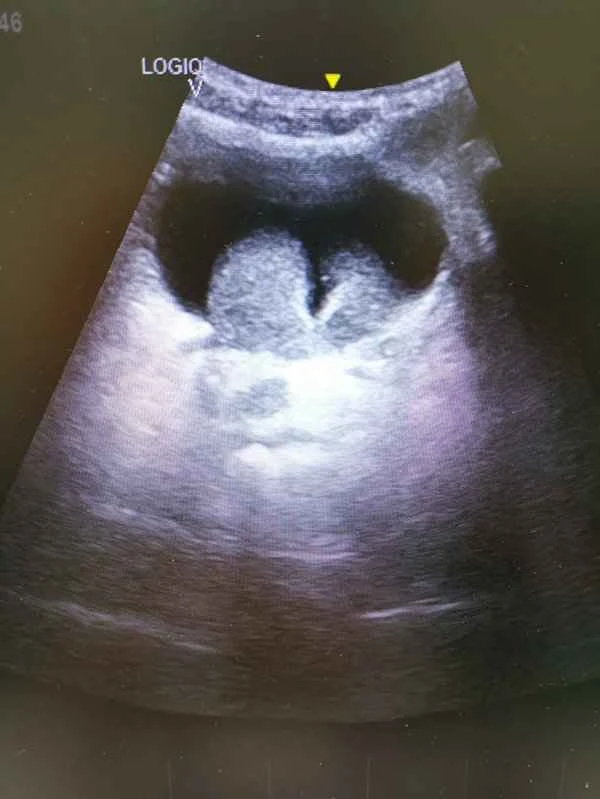

A scrotal ultrasound is a non-invasive examination used to observe the structures within the scrotum, including the testes, epididymis, and spermatic cord. It can help doctors diagnose various diseases, such as testicular torsion, epididymitis, and testicular tumors. The importance of this examination lies in its ability to help detect and diagnose diseases of the male reproductive system at an early stage, thus allowing patients to receive the best possible treatment.

A scrotal ultrasound examination typically involves scanning the scrotum with an ultrasound machine. The doctor then uses the images to determine if any abnormalities are present. This examination works by utilizing the physical properties of ultrasound waves; it generates images based on the differences in how different tissues reflect ultrasound waves, allowing doctors to observe subtle structural changes within the scrotum. While the procedure is relatively simple, the results are crucial for diagnosis and treatment.

After obtaining the examination results, the doctor will determine whether any abnormalities are present in the images and formulate a treatment plan accordingly. It is important to note that the results of a scrotal ultrasound need to be interpreted in conjunction with clinical symptoms and other examination results; a conclusion cannot be drawn based on a single examination result. Patients should follow their doctor's instructions before the examination to ensure its accuracy.